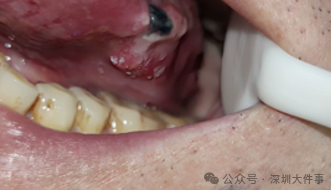

然而,当陈先生照镜子,发现小疙瘩已经长成了“小菜花”,凹凸不平,边缘模糊。在南方医科大学深圳医院颌面外科,医生一看发现情况不对,立即安排他做了一个局麻活检。

这个长在他舌头左侧,硬币大小、如菜花般的肿块,被诊断为“舌恶性肿瘤”,已向舌腹、口底扩散,属临床Ⅱ期。